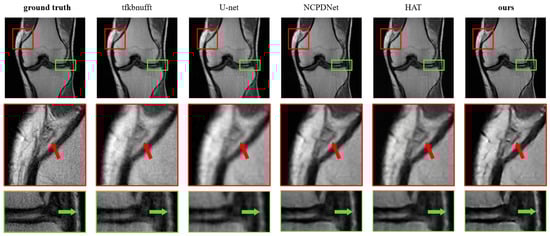

Super-Resolution Reconstruction Approach for MRI Images Based on Transformer Network

by Xin Liu, Chuangxin Huang, Jianli Meng, Qi Chen, Wuzheng Ji and Qiuliang Wang

AI 2025, 6(11), 291; https://doi.org/10.3390/ai6110291 - 14 Nov 2025

Magnetic Resonance Imaging (MRI) serves as a pivotal medical diagnostic technique widely deployed in clinical practice, yet high-resolution reconstruction frequently introduces motion artifacts and degrades signal-to-noise ratios. To enhance imaging efficiency and improve reconstruction quality, this study proposes a Transformer network-based super-resolution framework [...] Read more.

Magnetic Resonance Imaging (MRI) serves as a pivotal medical diagnostic technique widely deployed in clinical practice, yet high-resolution reconstruction frequently introduces motion artifacts and degrades signal-to-noise ratios. To enhance imaging efficiency and improve reconstruction quality, this study proposes a Transformer network-based super-resolution framework for MRI images. The methodology integrates Nonuniform Fast Fourier Transform (NUFFT) with a hybrid-attention Transformer network to achieve high-fidelity reconstruction. The embedded NUFFT module adaptively applies density compensation to k-space data based on sampling trajectories, while the Mixed Attention Block (MAB) activates broader pixel engagement to amplify feature extraction capabilities. The Interactive Attention Block (IAB) facilitates cross-window information fusion via overlapping windows, effectively suppressing artifacts. Evaluated on the fastMRI dataset under 4× radial undersampling, the network demonstrates 3.52 dB higher PSNR and 0.21 SSIM improvement over baselines, outperforming state-of-the-art methods across quantitative metrics. Visual assessments further confirm superior detail preservation and artifact suppression. This work establishes an effective pipeline for high-quality radial MRI reconstruction, providing a novel technical pathway for low-field MRI systems with significant research and application value. Full article